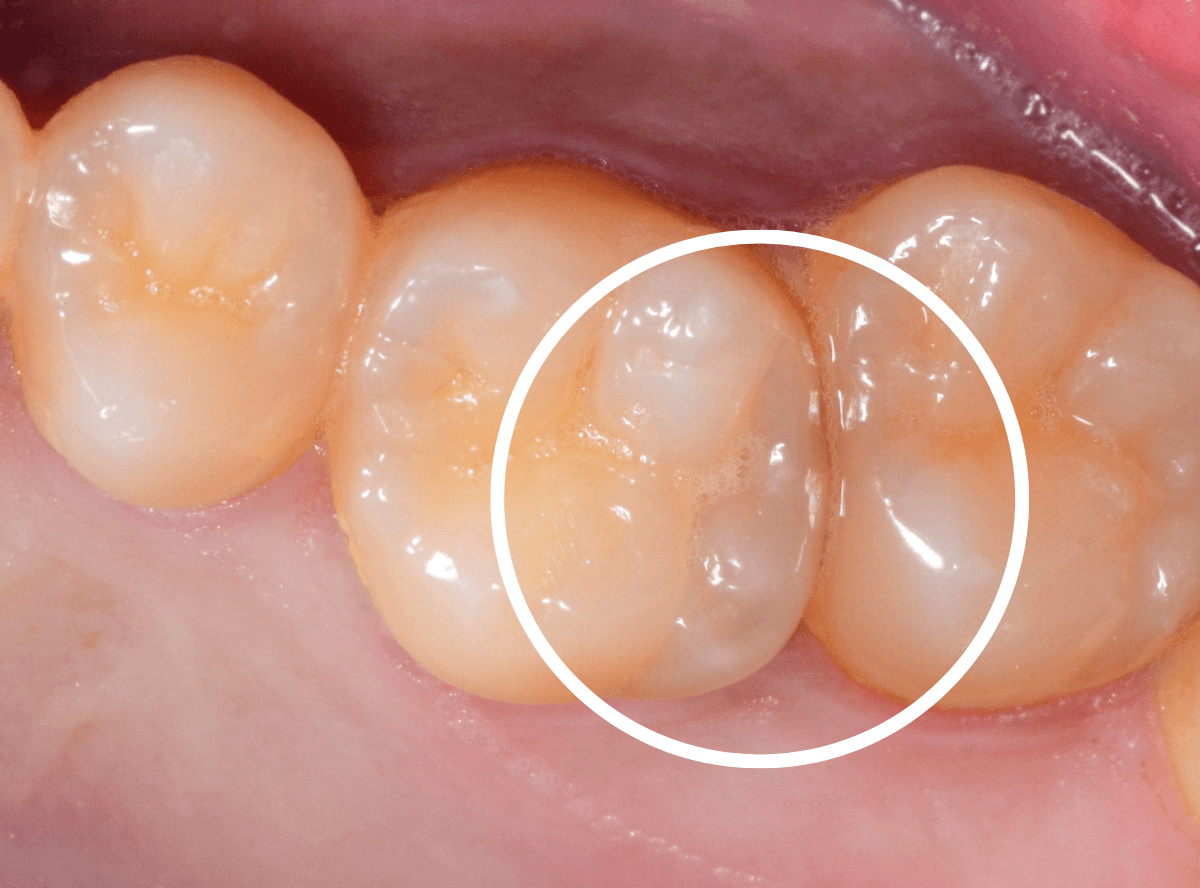

Case.16 白濁でわかる虫歯

他の歯の治療希望で来院された患者さんです。

お口の中全体をチェックしていると、白濁した歯が見つかりました。

中で深い虫歯になっている可能性が高いです。

レントゲン写真で確認します。

すると、怪しい歯の部分の他に、手前の歯との間にも虫歯がある事がわかりました。

もう一度お口の中を確認すると、レントゲンで虫歯があるとわかった部分には物がつまっていました。